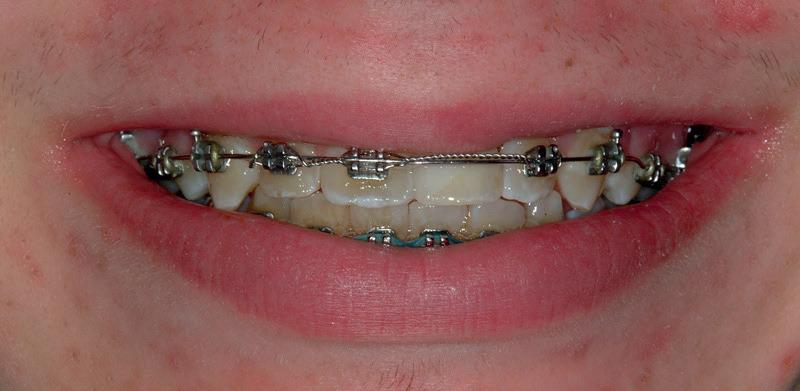

RECONFIGURAREA suportului osos implantar. În cazul prezentat, după ani de terapie ortodontică incorect executată, dezvoltarea dentară a pacientului a complicat obținerea unui zâmbet estetic. S-a reanalizat și s-a optat pentru abordare interdisciplinară care cuprinde chirurgia parodontală, un al doilea tratament

ortodontic și protetica pentru a oferi îngrijirea comprehensivă.